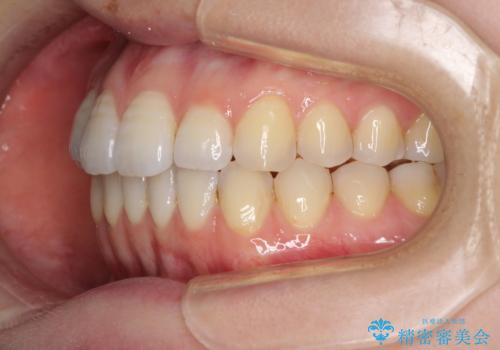

オープンバイトのインビザラインを用いた再矯正

- 矯正治療の後戻りを気にして来院された患者様です。

オープンバイト(前歯の開咬)と下顎骨の偏位による不正咬合が認められました。

骨格の偏位による不正咬合は改善しきれないことを理解いただいた上で、インビザラインにて矯正治療を行うこととしました。

オープンバイトは後戻りを起こしやすいため、極力そのリスクを軽減するため、奥歯を圧下させるように治療を進めていきました。

下顎骨の偏位が顕著であったため、上下の正中を合わせることはできませんでしたが、患者様には大変満足していただきました。